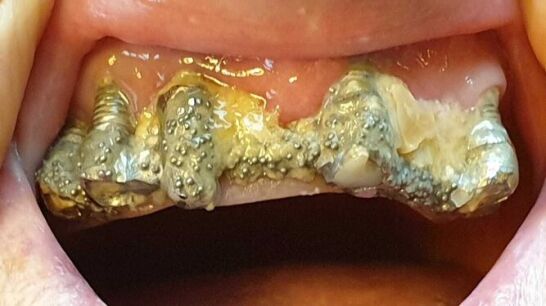

Cuenta que acudió por primera vez a la clínica en 2010 para colocarse implantes dentales en la parte superior de la boca, pero que el dentista le recomendó hacerlo también en la mandíbula inferior. Así, le extrajeron todos los dientes para susituirlos por piezas de porcelana, pero los implantes se deterioraban, se rompían y se infectaban constantemente. Por ello, le realizaron numerosas reparaciones y le recolocaron la prótesis varias veces, causándole lesiones en la boca.

Asegura que los arreglos que le hicieron en las coronas rotas a veces "duraban menos de una hora" y que, en 2016, tras más de 80 visitas al centro donde fue atendida por una decena de profesionales distintos, la clínica le comunicó que no se haría cargo de más reparaciones. A partir de entonces tendría que asumir el coste ella misma.